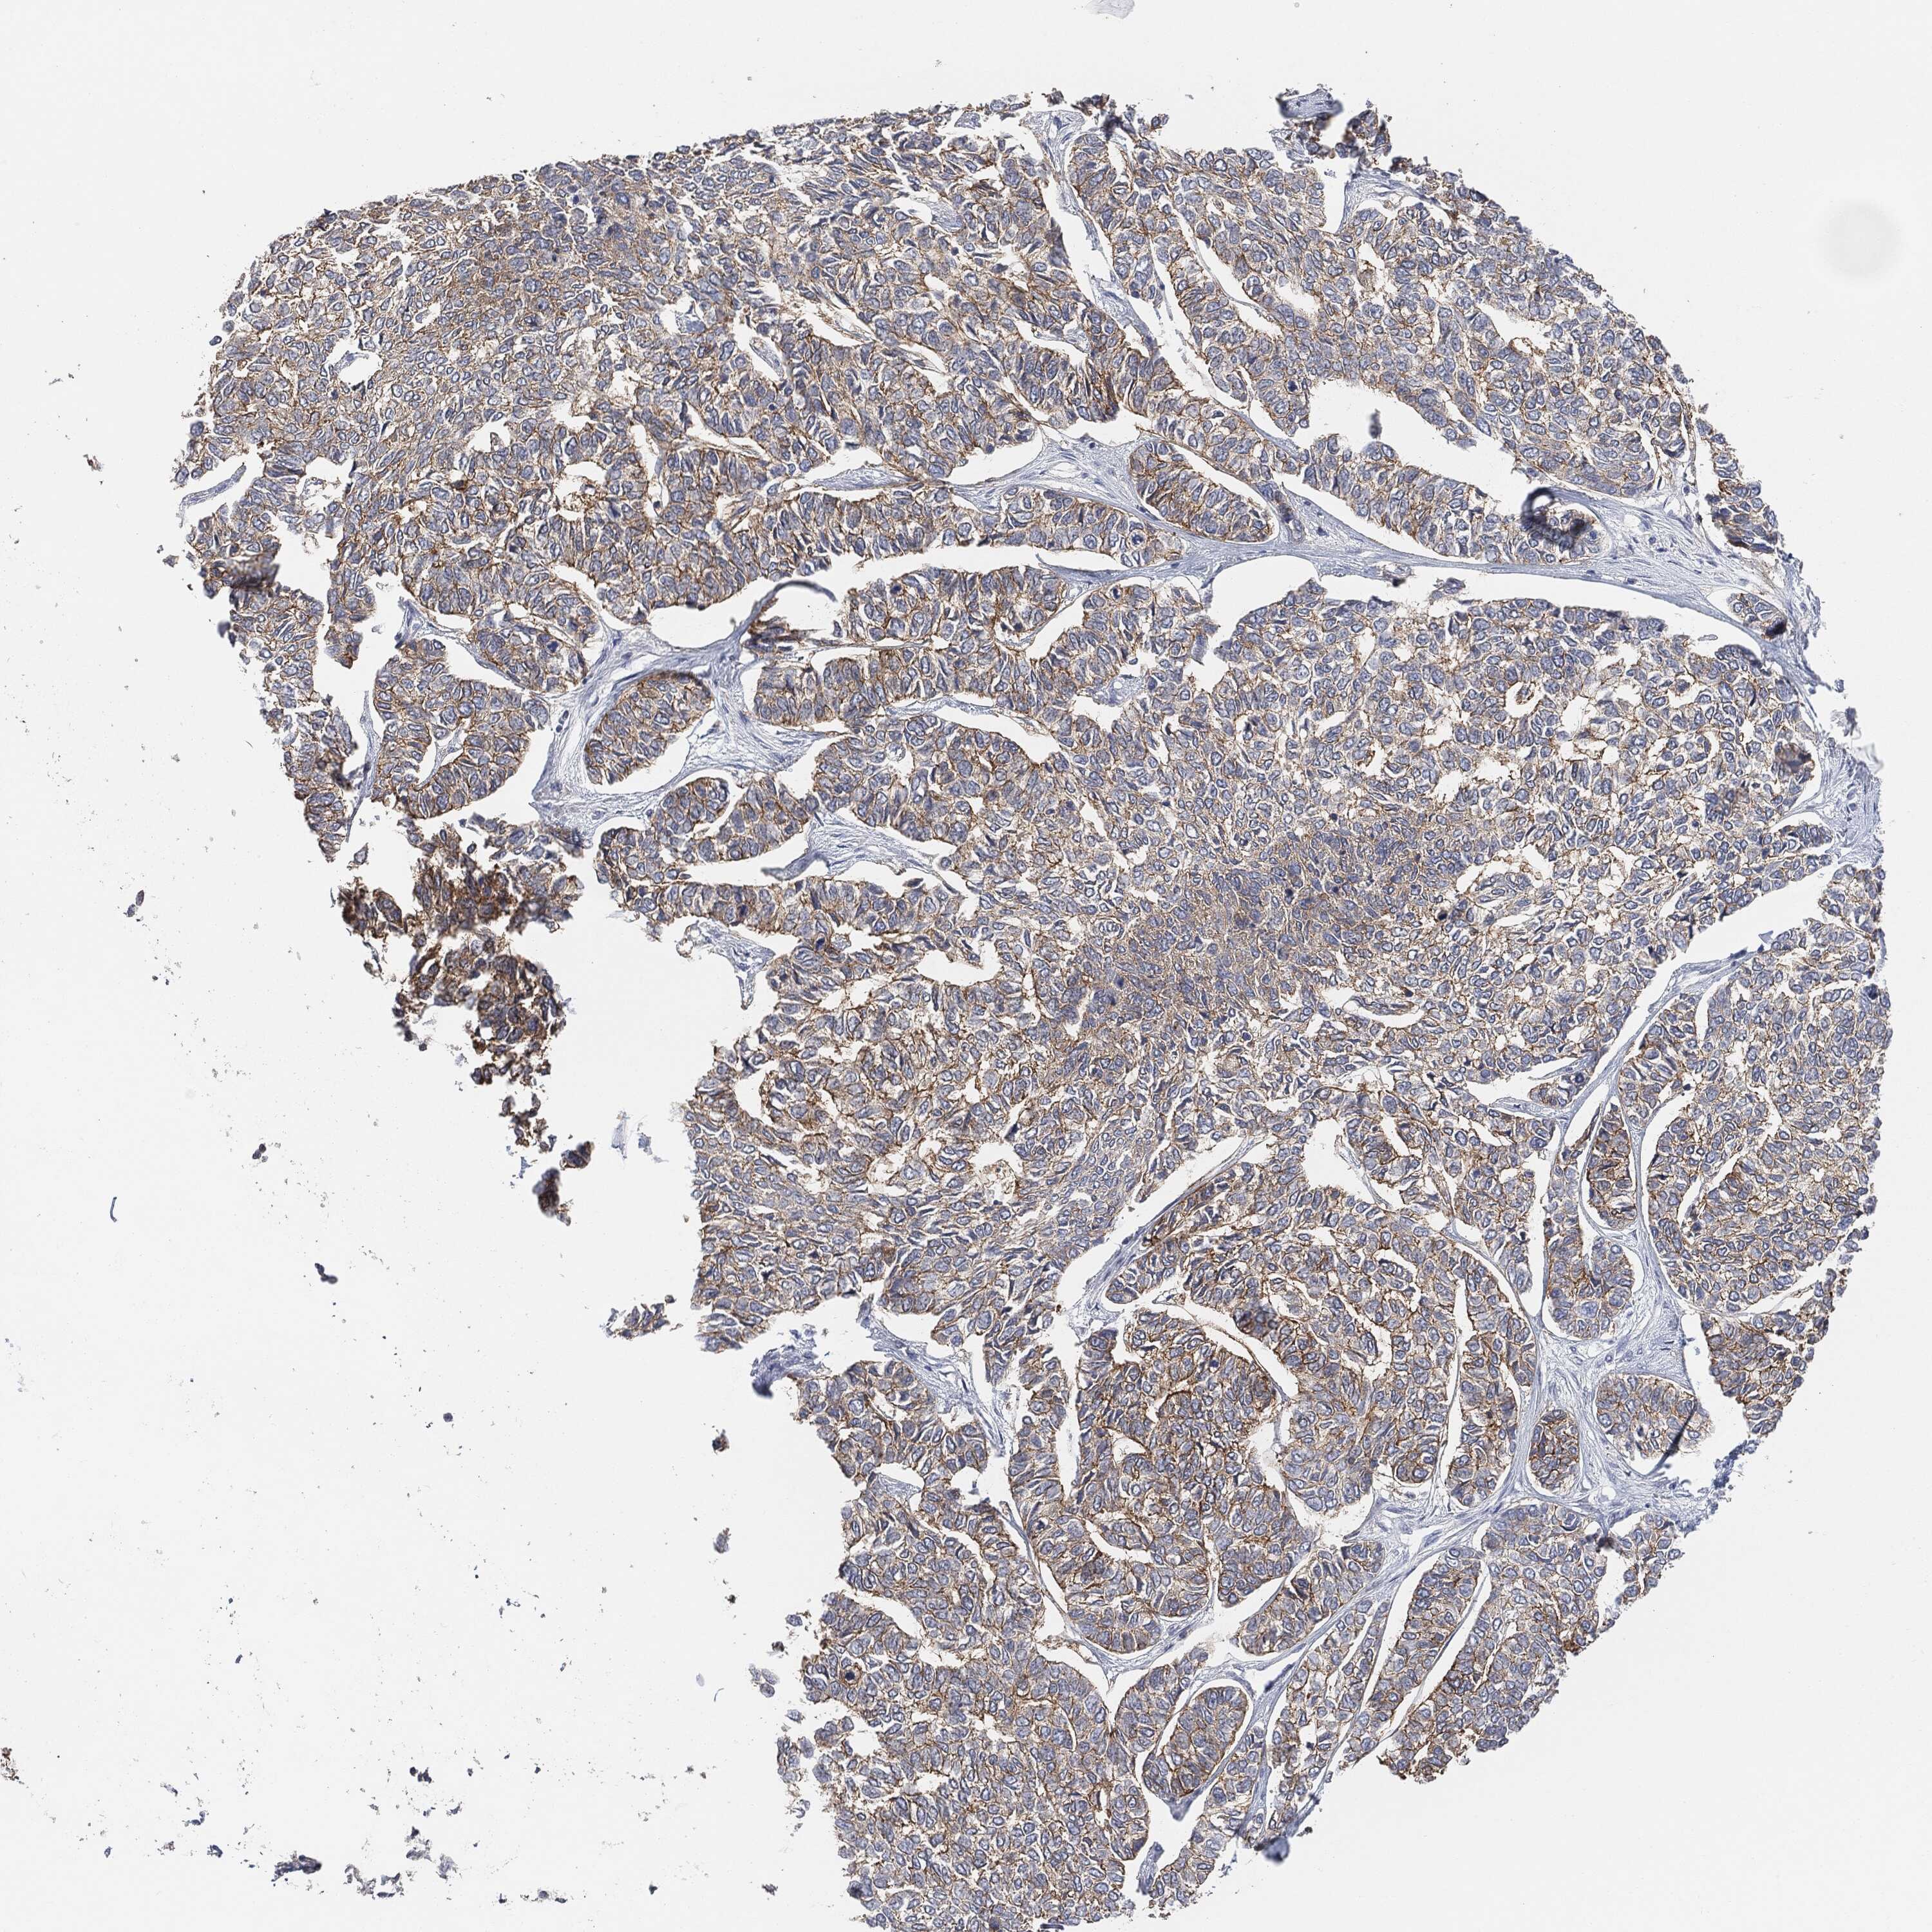

SKIN CANCER - Protein expressioni

A mouse-over function shows sample information and annotation data. Click on an image to view it in a full screen mode. Samples can be filtered based on level of antibody staining by selecting one or several of the following categories: high, medium, low and not detected. The assay and annotation is described here.

Antibody stainingi

Antibody staining in the annotated cell types in the current human tissue is reported as not detected, low, medium, or high, based on conventional immunohistochemistry profiling in selected tissues. This score is based on the combination of the staining intensity and fraction of stained cells.

Each image is clickable and will lead to virtual microscopy that enables deeper exploration of all samples and also displays staining intensity scores, fraction scores and subcellular localization as well as patient and tissue information for each sample.

Squamous cell carcinoma, NOS